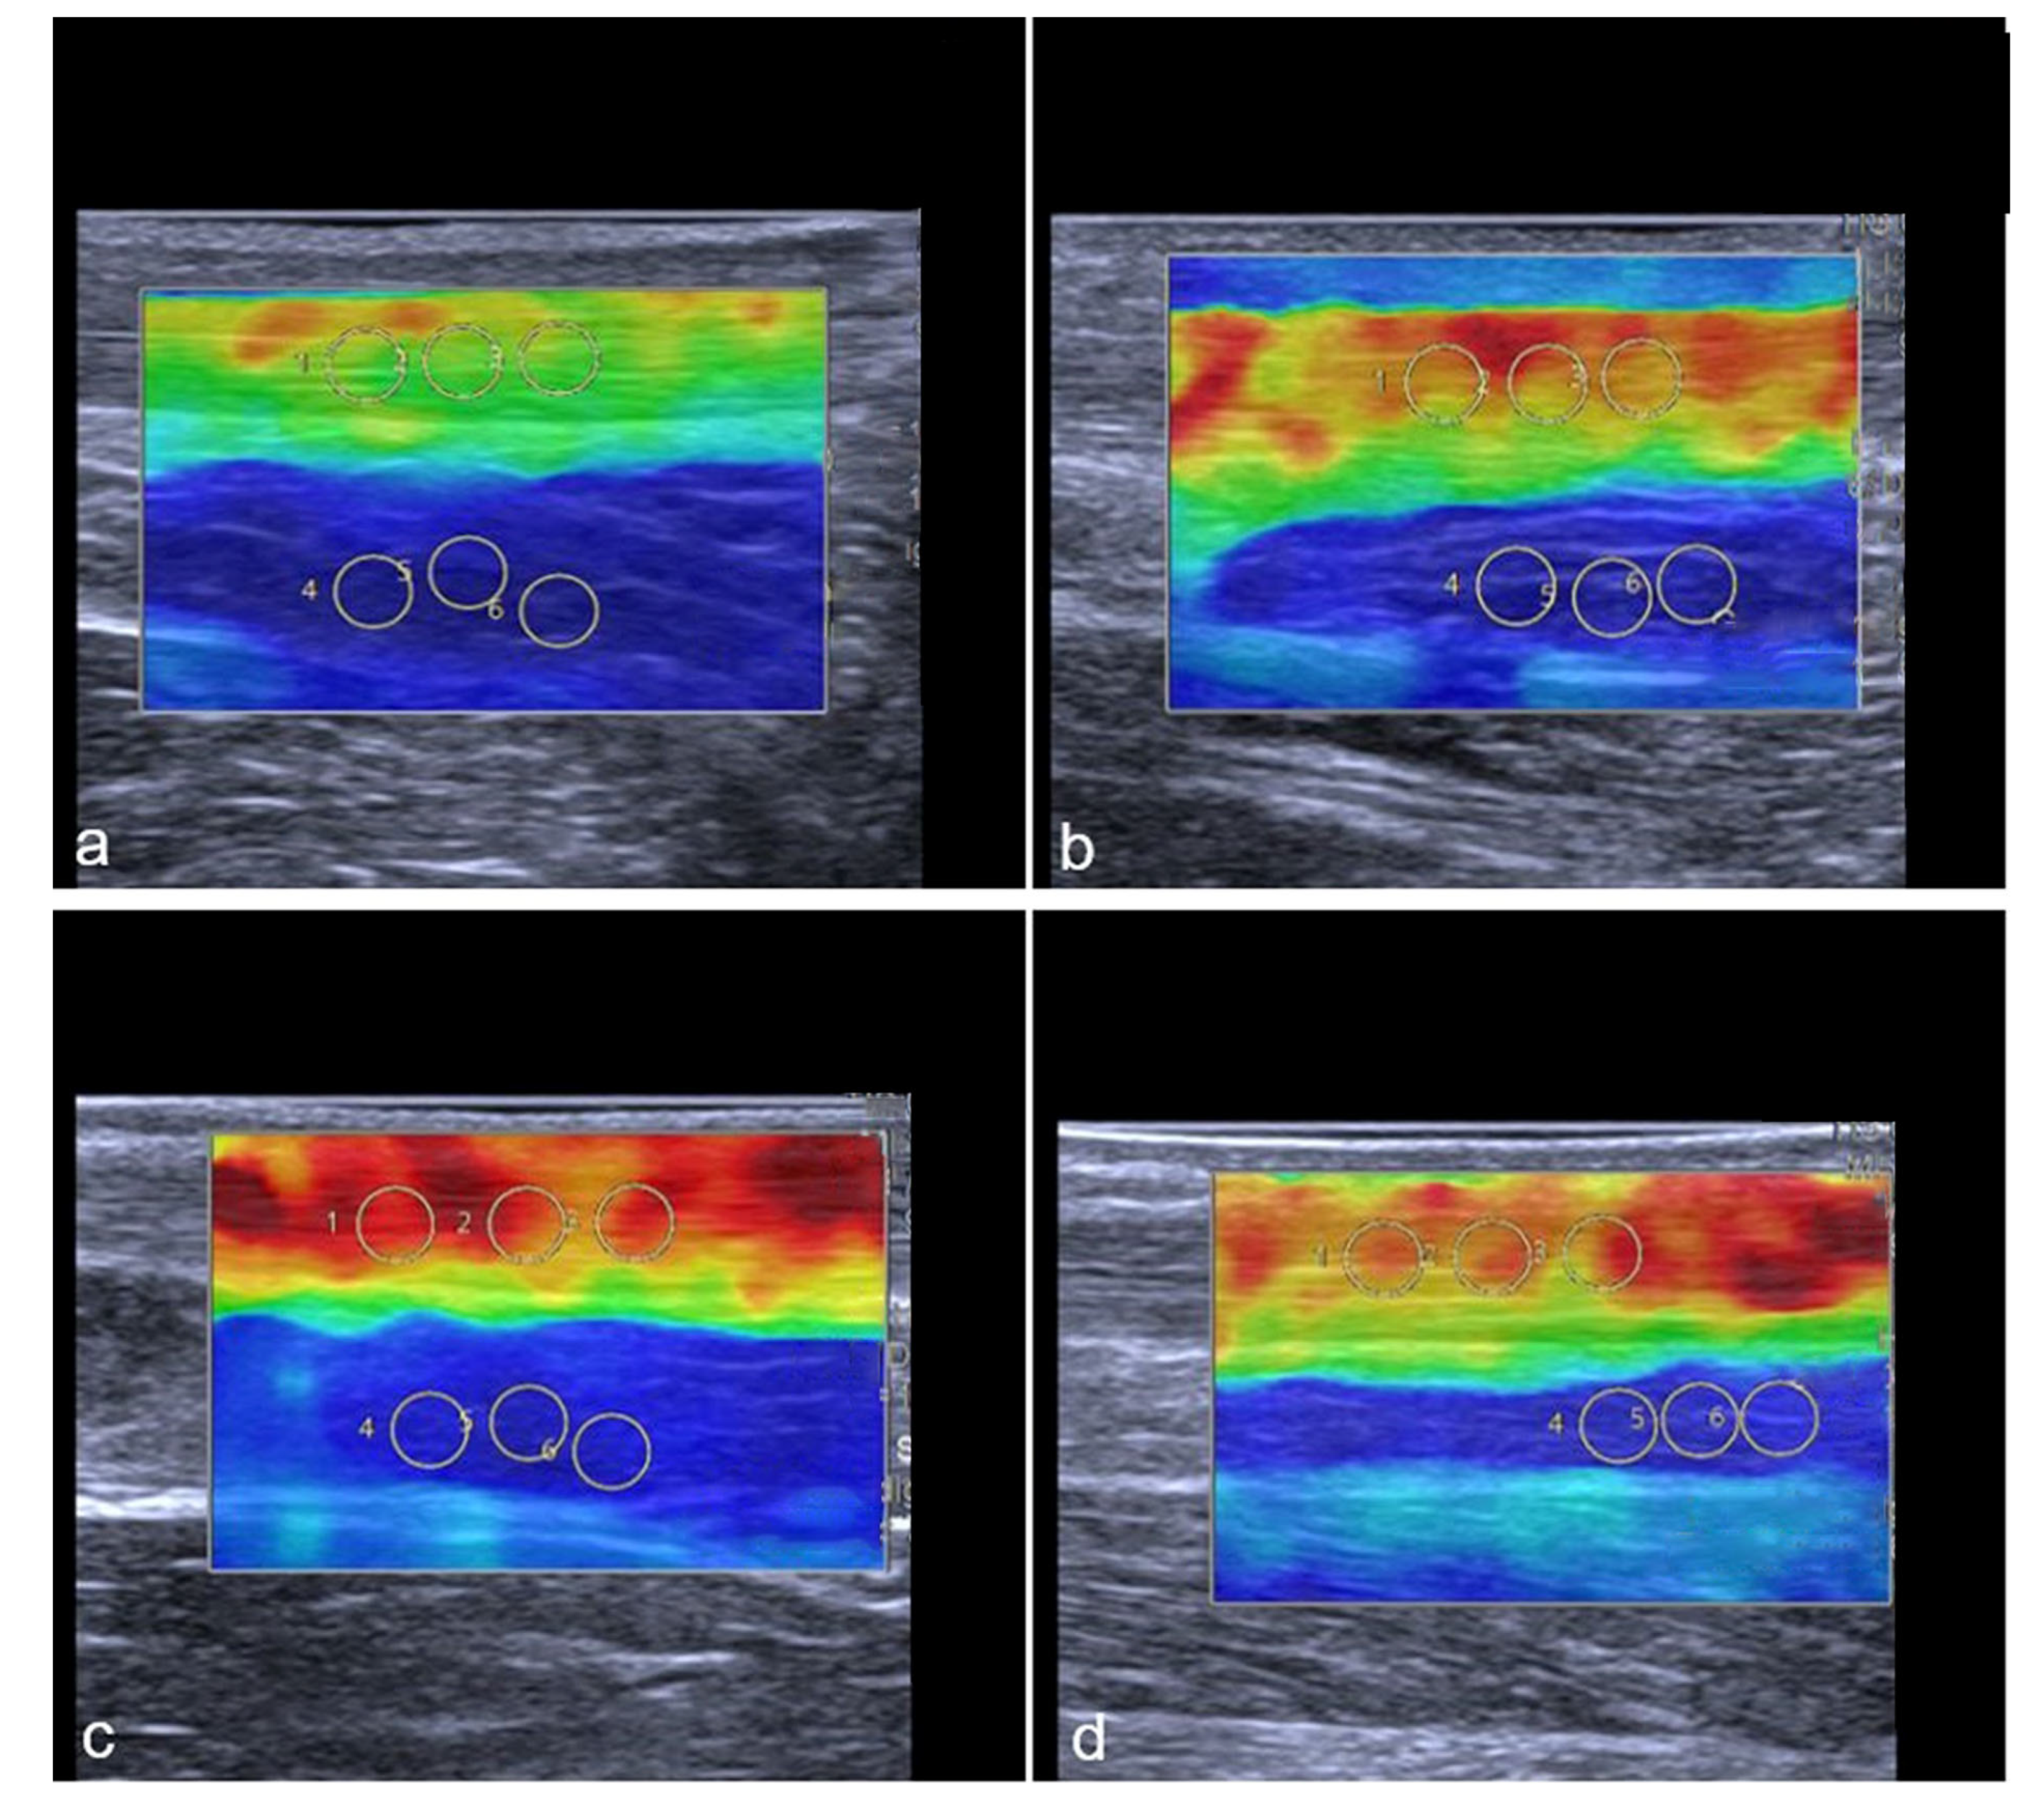

Representative images of the change in the tendon stiffness are shown in Figure 6.

Figure 6.

Representative SWE images of two professional female athletes prior and after standardized treadmill. Color-coded map of Achilles tendon is shown in (a–d). Green corresponds with softer tendon tissue and lower SWS values. Subfigures (a–d) show the same female athlete, (a,c) demonstrate pre-exercise images. (b,d) demonstrate post-exercise images. The color-coded SWE maps in Figure 6 present the AT stiffness of two athletes. In the 2D-SWE color maps, red is coded as hard tissue and blue as soft. The overall SWS was calculated using four images with three regions per structure, given an overall number of 12 measurements per tendon or muscle. In this figure, a female athlete with lower baseline SWS (a) showed an increase in stiffness after exercise (b), while another athlete with higher baseline stiffness (c) showed a slight reduction in SWS (d) (Gastrocnemius muscle not shown in this images).